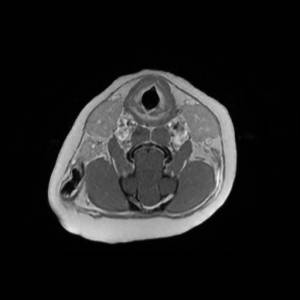

Main Gallery

Playing with a photo gallery function. It is possible to have multiple galleries, each within a namespace.